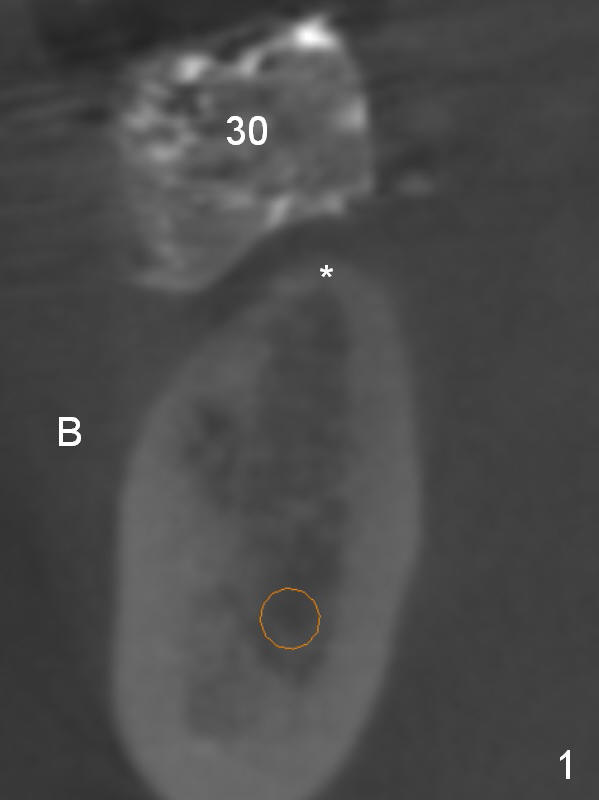

A 50-year-old lady has lost the teeth #30 and 31 for long time with supraeruption of the teeth #2 and 3. Orthodontic intrusion results in enough space for #30 implant. CT coronal section shows that the crest at #30 is lingualized (Fig.1 *). If osteotomy starts at the crest (Fig.2 red), the implant will be lingually inclined (Fig.3 green); an angled abutment has to be used (red).